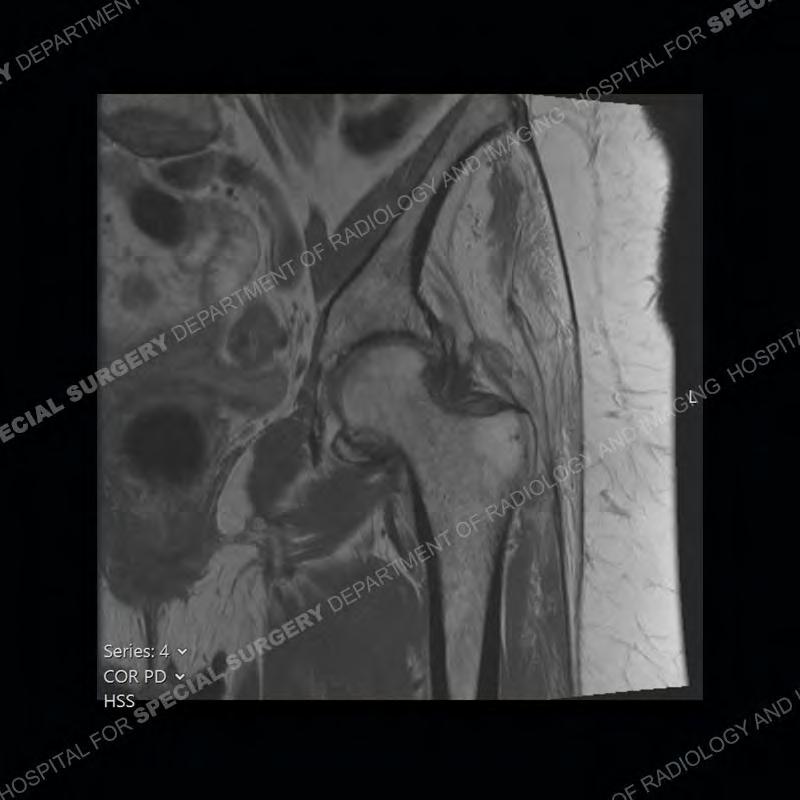

The radiograph is not particularly contributory in this case. The MRI demonstrates markedly abnormal architecture of the gluteus minimus and anterolateral band of the gluteus medius. Portions of the tendons are high signal, portions are highly attenuated, and portions are disrupted. A large, complex fluid collection is present in the adjacent soft tissue.

Diagnosis: Gluteal Tendinosis and Disruption with Complex Trochanteric Bursal Collection

Not as much of a diagnostic dilemma as many of the other cases shown but just a nice example of the pathology seen of the gluteal tendons and a cause of trochanteric pain. Although, frequently thought of in isolation, trochanteric bursitis or bursal thickening is much more commonly a reactive change to underlying pathology of the subjacent gluteal tendons. The gluteus medius is divided into a posterior band and an anterolateral band. Tendinosis and partial tearing very commonly will involve the gluteus minimus and especially the more posterior fibers and then propagate into the anterior lateral band of the gluteus medius. Involvement of the posterior band of the medius is much less common and engenders a marked degree of functional impairment.

The bursae about the greater trochanter can be a little bit confusing especially given the terminology. Trochanteric bursitis is implied to mean the subgluteus maximus bursa which is present deep to the maximus and just lateral/superficial to the trochanter. That is the bursa involved in this case. In this case the complexity of the bursa relates to the tendon tearing with inflammatory change and probably hemorrhage accounting for the complexity. Two other, less frequently involved bursa are also present. The subgluteus medius and subgluteus minimus bursa are found just deep to the named tendons. Although pathology does frequently follow the previously described pattern it is possible to have isolated pathology to either the medius or minimus.